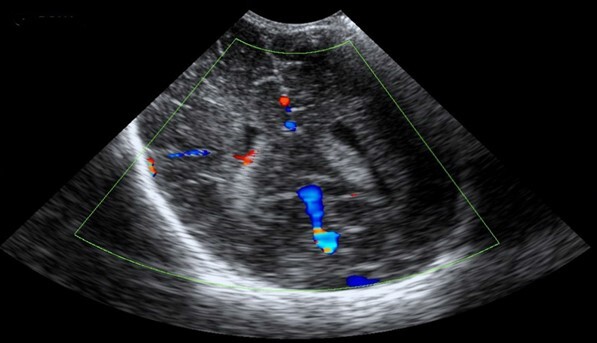

Neonatology Split Choroid Doppler Image